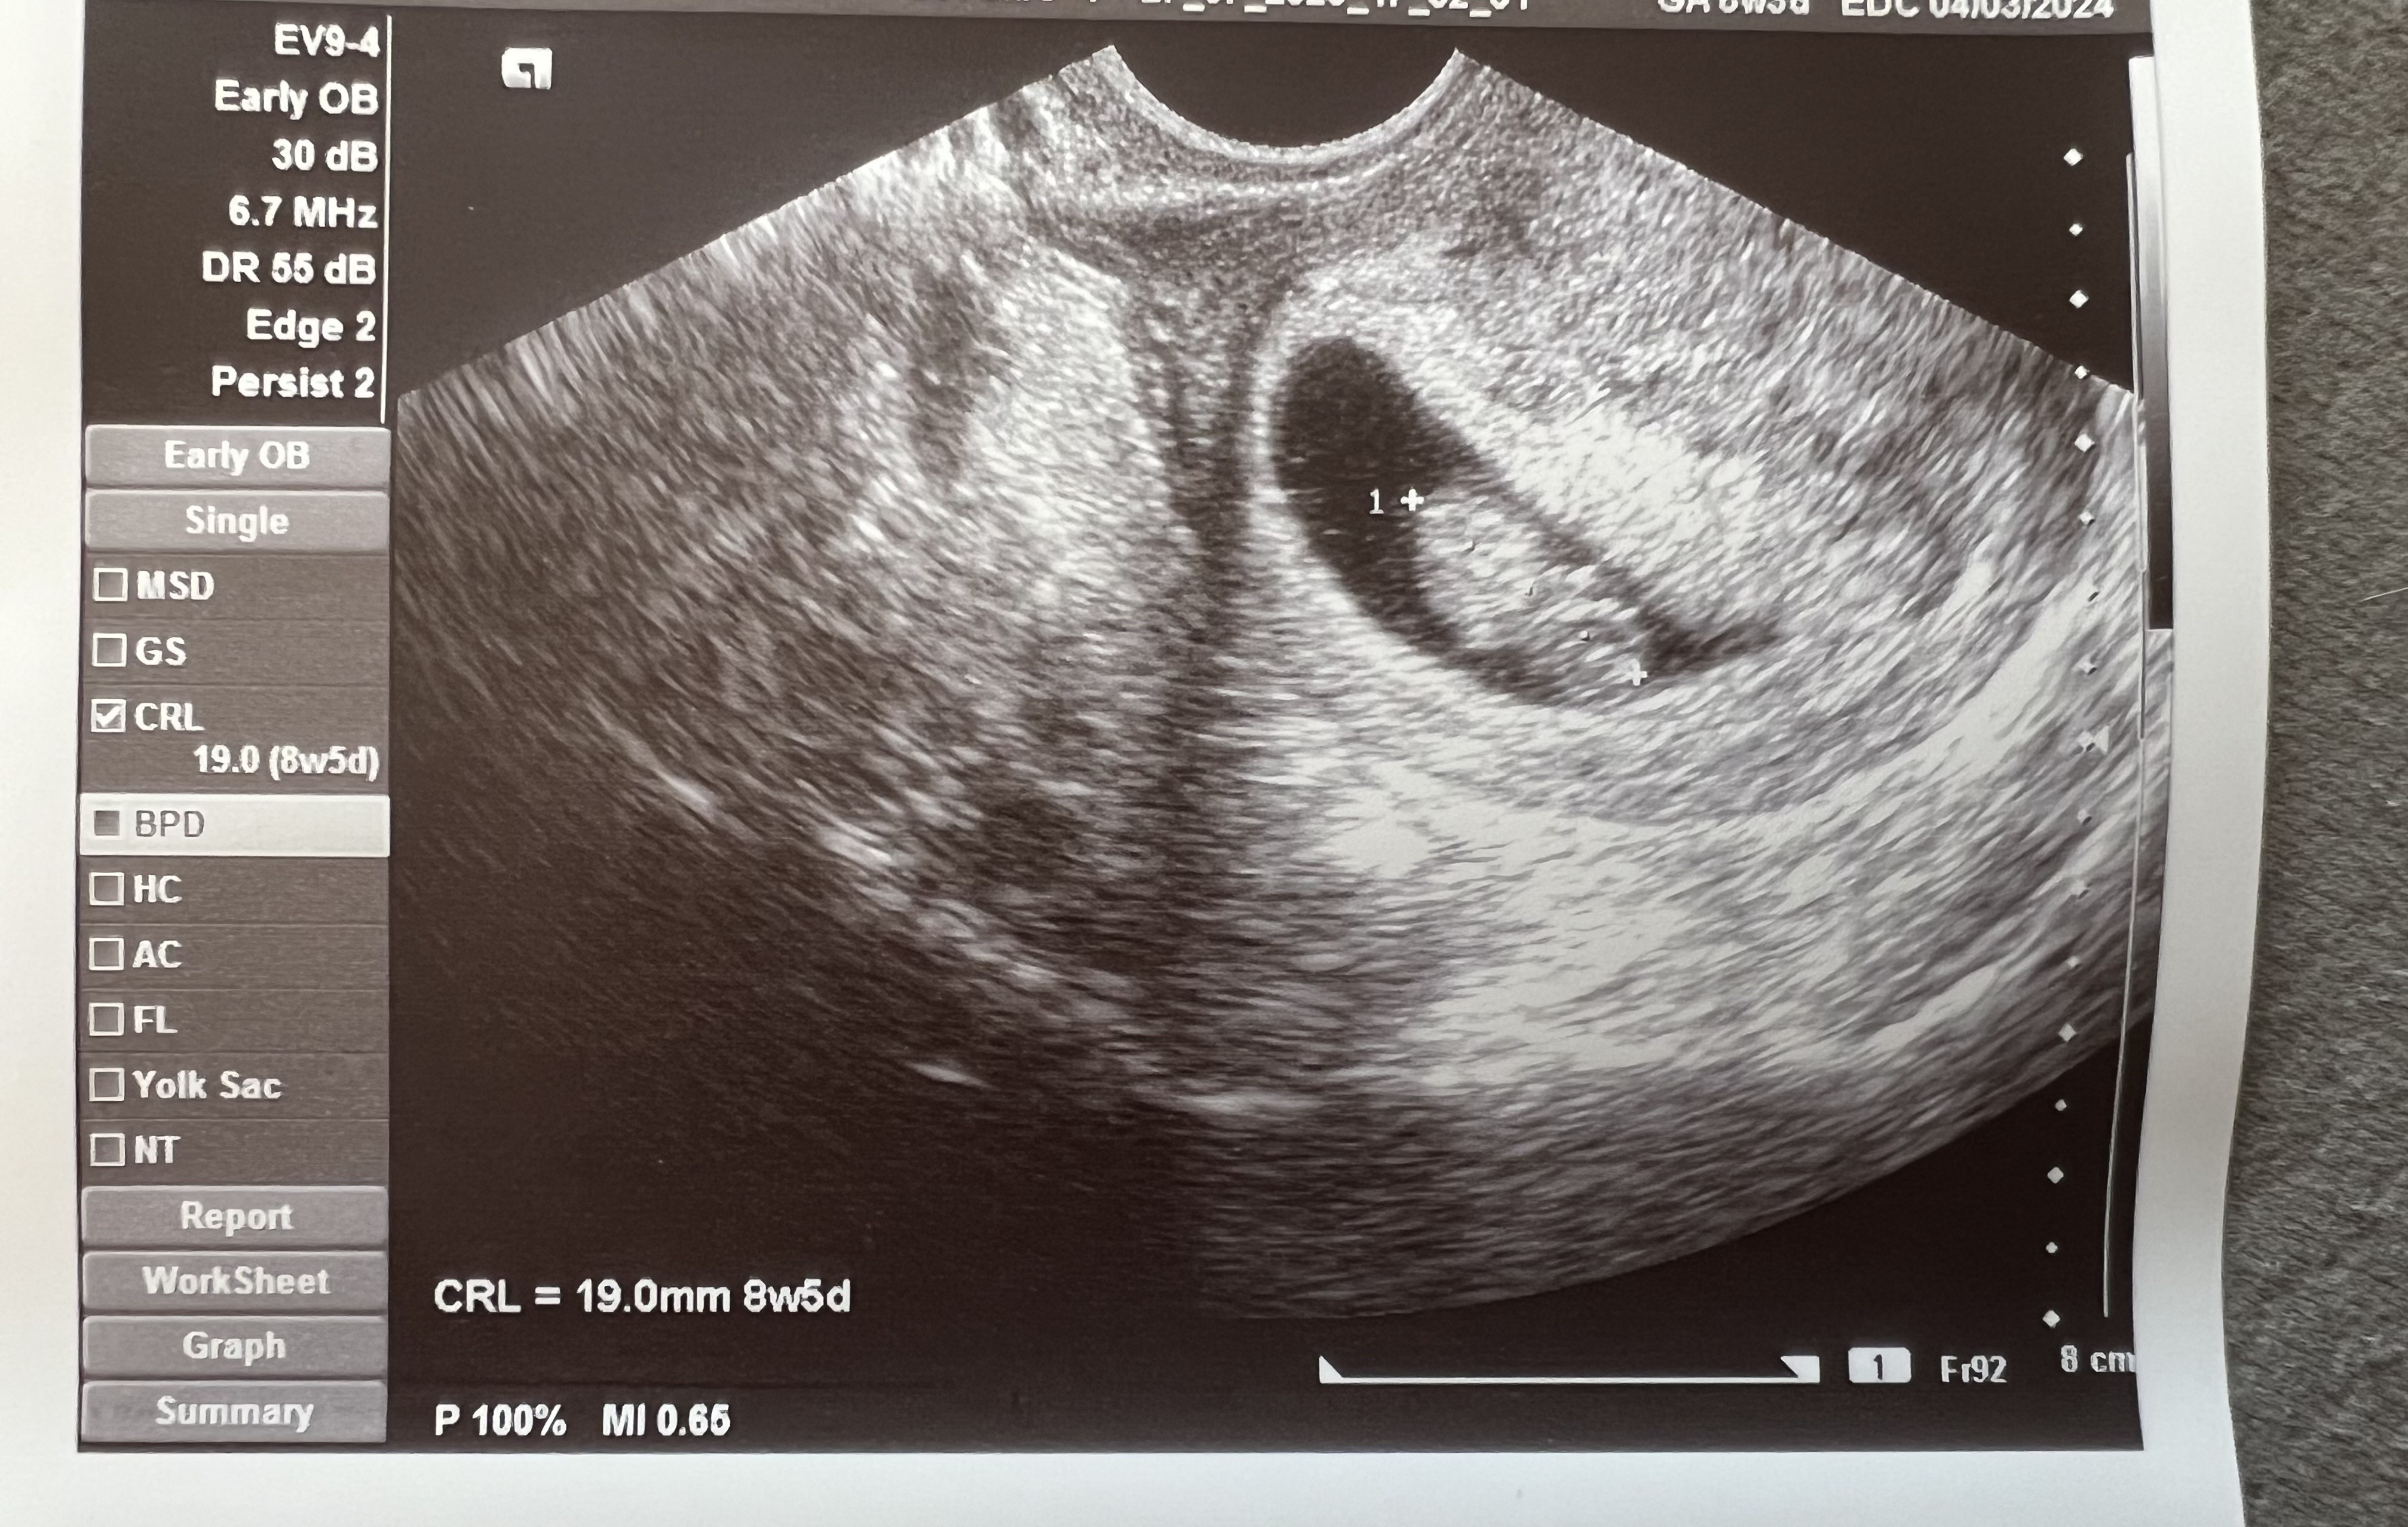

Super i gratulacjeJa już po wizycie, maluch ma 1,9 cm i serce jak dzwonjestem taka szczęśliwa, chyba serio tym razem będzie wszystko dobrze

Ale duży bobikJa już po wizycie, maluch ma 1,9 cm i serce jak dzwonjestem taka szczęśliwa, chyba serio tym razem będzie wszystko dobrze

SuperJa już po wizycie, maluch ma 1,9 cm i serce jak dzwonjestem taka szczęśliwa, chyba serio tym razem będzie wszystko dobrze

Cudowny bobasek rośnieJa już po wizycie, maluch ma 1,9 cm i serce jak dzwonjestem taka szczęśliwa, chyba serio tym razem będzie wszystko dobrze

ŚwietnieJa już po wizycie, maluch ma 1,9 cm i serce jak dzwonjestem taka szczęśliwa, chyba serio tym razem będzie wszystko dobrze

To już nie taki maluch!Ja już po wizycie, maluch ma 1,9 cm i serce jak dzwonjestem taka szczęśliwa, chyba serio tym razem będzie wszystko dobrze

Ale piękna dzidziaJa już po wizycie, maluch ma 1,9 cm i serce jak dzwonjestem taka szczęśliwa, chyba serio tym razem będzie wszystko dobrze